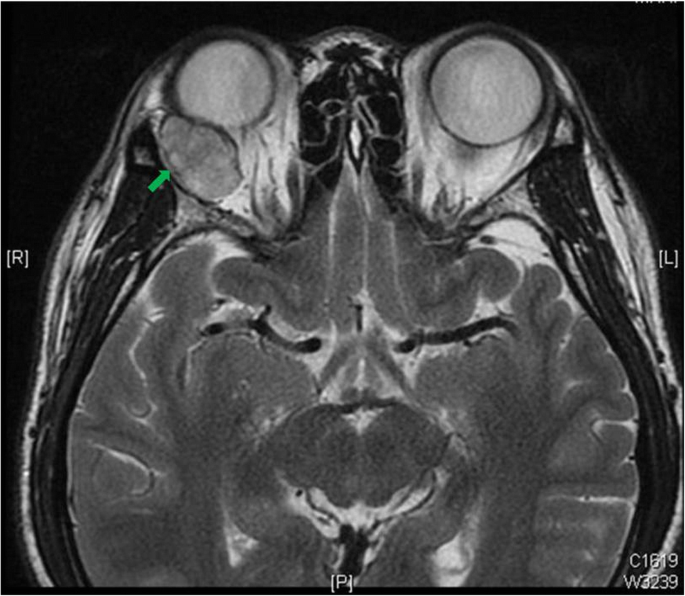

Magnetic resonance imaging (MRI) showed a well circumscribed, homogenous, 16 × 24 × 22 mm large, oval-shaped intraconal mass extended from superior temporal side of the right orbit (Fig. 2). The patient then received removal of tumor through lateral orbitotomy and histopathology confirmed a pleomorphic adenoma of the orbit.